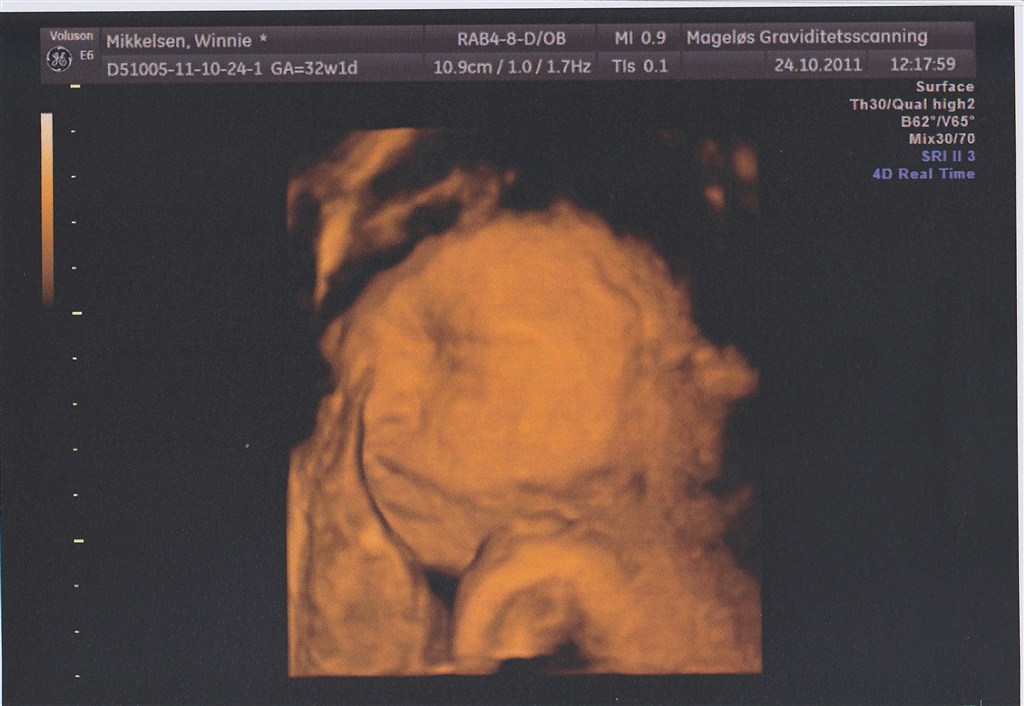

Selve 3D-scanningen gik dog lidt mere besværligt. Min moderkage ligger fortil (dog heldigvis højt), og lillepigen lå med hovedet vendt ind imod den. Jeg drak koldt vand og hoppede lidt, men det hjalp ikke meget.

Da jeg kom tilbage havde hun vendt hovedet lidt - stadig ikke ideelt men nok til at vi kunne få lidt billeder halvt i profil.

Det var sjovt at se det lille ansigt med den lille nedadvendte mund (præcis som min storesøsters datter har) og de lange øjenvipper. Det vigtigste var dog at hun havde det godt derinde og at vi fik bekræftet at alt var ok

Vedhæftede fotos (klik for at se i fuld størrelse)